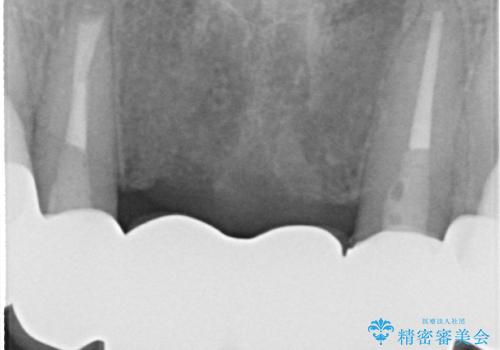

- 仮歯の製作、古い土台(メタルコア)の除去まで行い、根管治療は専門医に依頼

→根管治療終了後、ファイバーコアを築造し、新しいセラミックブリッジを製作した。

一見きれいにはいっているセラミックも、はずして中の状態をみるとひどいことが多い。これは、中の土台の状態や処理のクオリティは、短期的には問題を起こしづらく、患者さんには見えない部分だからです。